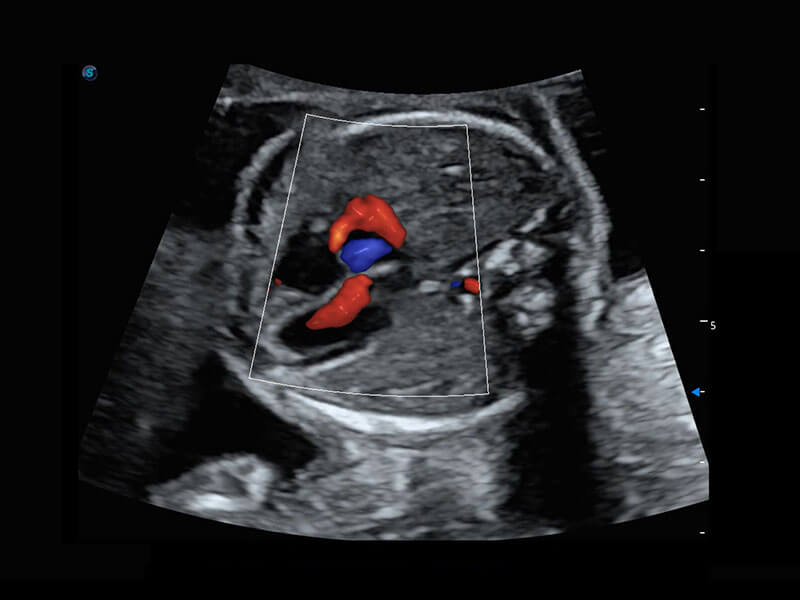

P60搭載一系列胎兒心臟成像技術(shù),實(shí)現(xiàn)精細(xì)的胎兒心臟評(píng)估。

四腔心血流